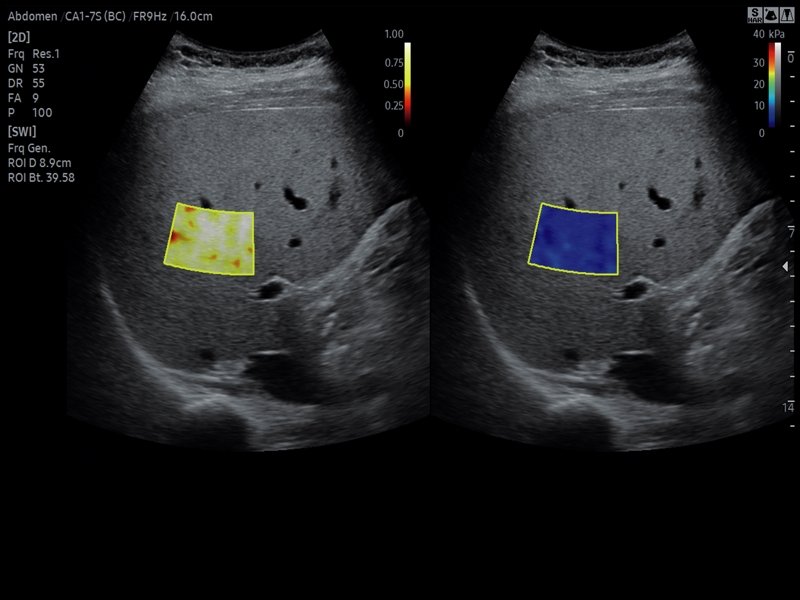

Как выглядит доля Риделя на УЗИ печени